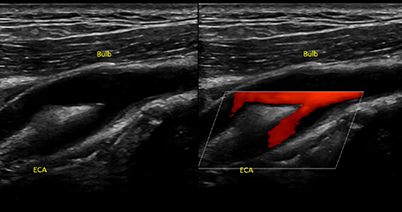

혈관의 벽 두께(IMT)를 측정: 혈관 벽이 두꺼워 졌는지를 확인하여 죽상동맥경화여부를 판단할 수 있습니다.

플라크의 여부: 지방 찌꺼기나 석회화 플라그가 있는지, 있다면 크기와 모양은 어떤지를 초음파로 체크할 수 있습니다.

혈류 속도와 방향: 혈류의 속도를 측정하고 장비에서 혈관에 컬러를 띄워 관찰하는데 협착의 유무나 얼마나 심한지를 평가 할 수 있습니다.